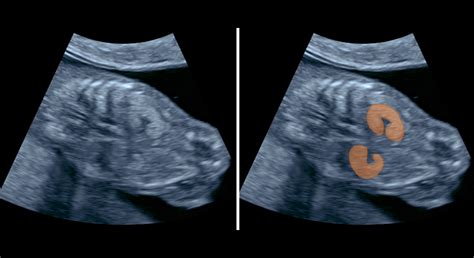

NT (Nuchal Translucency) - šijové prejasnenie je definované ako nahromadenie tekutiny v zátylku plodu na konci prvého a na začiatku druhého trimestra. Pri plodoch s Downovým syndrómom, s genetickými anomáliami, vážnymi chybami srdca a hrubých ciev alebo skeletálnymi dyspláziami sa na tomto mieste nachádza väčšie množstvo tekutiny, čo spôsobuje edém záhybu šije. Ten sa prejaví vysokými hodnotami NT. Hrúbka šijového prejasnenia je u zdravých plodov cca 1 až 2,5 milimetra (norma až do 3 mm).

Vyšetrenie sa musí vykonať v 11. až 13. týždni tehotenstva, presné stanovenie veku gravidity je základným predpokladom relevantného výsledku. Je rozdiel v hodnotách NT aj pre tieto tri týždne. Zároveň je pri meraní dôležitá poloha plodu (neutrálna), iná poloha hlavičky môže výsledky skresliť. Keďže sa jedná o veľmi presné meranie s malou toleranciou odchýlky (desatiny milimetra), štúdie potvrdzujú, že toto vyšetrenie môže urobiť len vyškolený sonografista s kvalitným ultrazvukom.